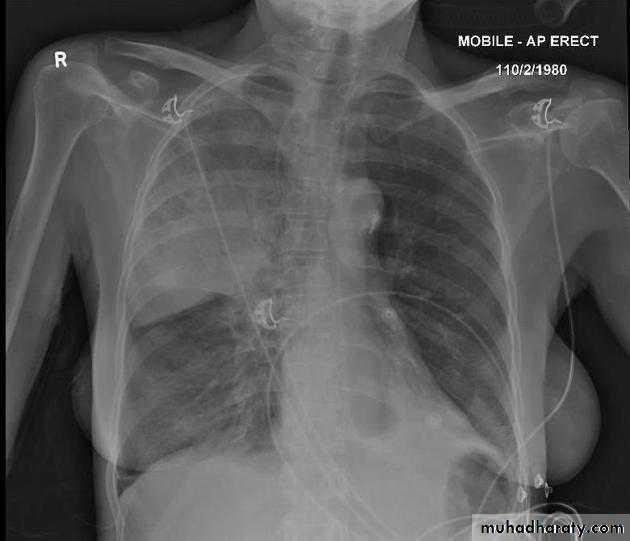

Left lower lobe collapse has distinctive features, and can be readily identified on frontal chest radiographs, provided attention is paid to the normal cardiomediastinal contours. The shadow cast by the heart does however make it harder to see than the right lower lobe collapse

Radiographic features

Left lower lobe collapseis readily identified in a well penetrated film of a patient with normal sized heart, but can be challenging in the typical patient with collapse, namely unwell patients, with portable (AP) often under-penetrated films, often with concomitant cardiomegaly. Features to be observed include :

triangular opacity in the posteromedial aspect of the left lung

edge of collapsed lung may create a 'double cardiac contour'

left hilum will be depressed

loss of the normal left hemidaphgragmatic outline

loss of the outline of the descending aorta

Non-specific signs indicating left sided atelectasis are usually also be present including:

elevation of the hemidiaphragm

crowding of the left sided ribs

shift of the mediastinum to the left

LT L L collapse